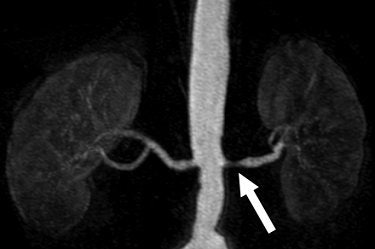

![]() |

| A 68-year-old man with severe stenosis of left renal artery. Anteroposterior maximum intensity projections of coronal 3D MR angiograms of abdominal aorta and renal arteries obtained with 0.2 mmol/kg of gadodiamide at 1.5 tesla (above) and 0.1 mmol/kg of gadodiamide at 3 tesla (below) show stenosis (arrow) equally well. |